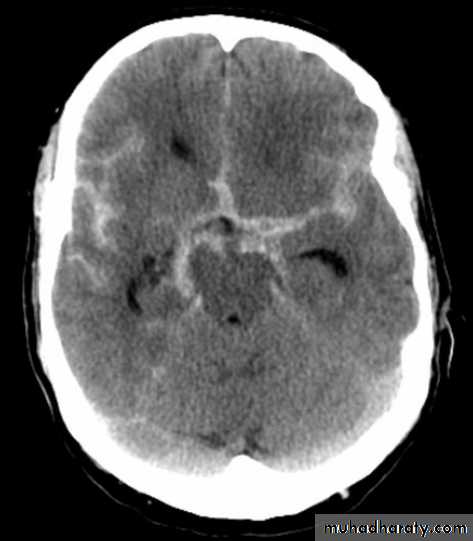

Subarachnoid hemorrhage

causesdue to ruptured aneurysm over 90 % of cases spcially at the circle of Willis .

ruptured AV malformation .

trauma .

CT finding

hyper density is seen within the SAS ( hyperdense sulci , being filled with clotted blood)

opacified inter hemispheric fissure ( become white & more dense )

opacification of the falx cerebri .

SAH

White sulciOpacified IHF